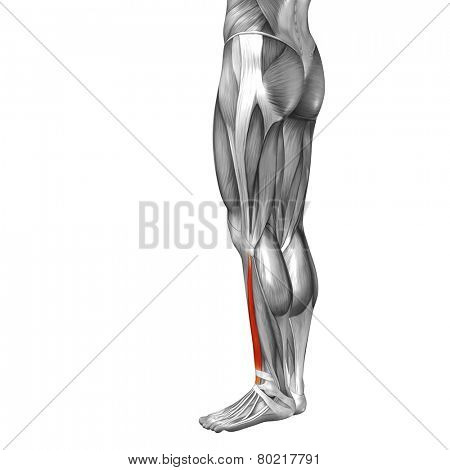

Extensor